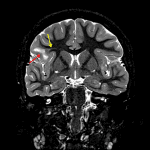

Age: 10

Sex: Female

Indication: Epilepsy

- Area of nonmasslike T2/FLAIR signal hyperintensity involving the cortex and juxtacortical white matter of the right inferior frontal gyrus and more subtle T2/FLAIR hyperintense signal radiating deep toward the ventricular margin

- Associated blurring of the gray-white interface

- No corresponding enhancement or restricted diffusion

Focal cortical dysplasia (FCD)